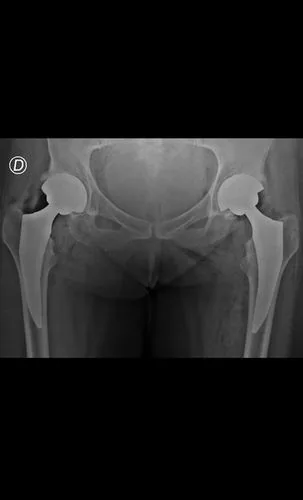

Preoperatorio

Postoperatorio

Artroplastia total bilateral de cadera en un solo tiempo quirúrgico. Alta hospitalaria a las 24 horas, deambulando con andador. Excelente restauración de la biomecánica articular bilateral.